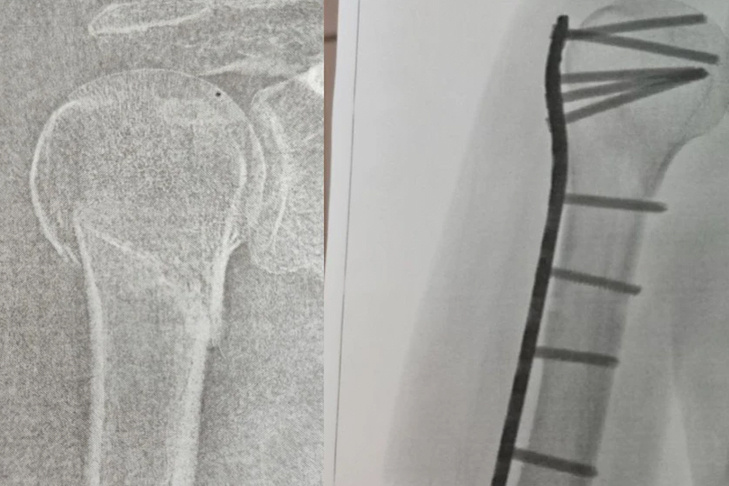

Муж Натальи вызвал скорую помощь. Медики забрали женщину, дали обезболивающее и наложили шину. В травмпункте рентген показал закрытый перелом плечевой кости со смещением отломков. Сибирячки пришлось проводить операцию — вставлять пластину и штифты.